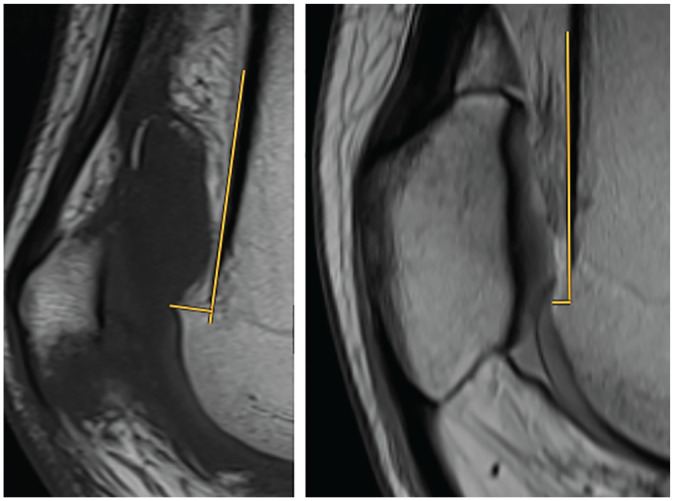

Methods: This study evaluated 363 knees with trochlear dysplasia that were scheduled to undergo surgery for the treatment of patellar instability at a single institution. All patients underwent preoperative true lateral radiography and magnetic resonance imaging (MRI). There were 2 independent reviewers who analyzed the supratrochlear spur height by measuring the distance between a tangent at the anterior femoral cortex and the most prominent point of the trochlea on sagittal MRI as well as other common patellofemoral parameters. All MRI scans were assessed for full-thickness cartilage lesions.